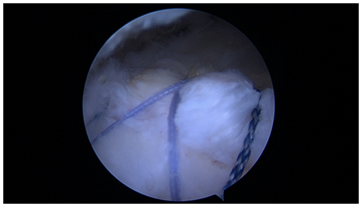

A promising technique for small or partial tears (PASTA) is a single tunnel repair (Figure 3). As demonstrated, this repair can create excellent coaptation of the tendon, with added strength from suture grasping stitches. A single tunnel in small repair area can provide “2 for 1” fixation points relative to a single anchor with a true transosseous, circumferential stitches rather than a transosseous equivalent construct with multiple anchors. It is likely that lateral anchors in this clinical situation add little value relative to their cost.

Figure 3 Single tunnel repair for a small rotator cuff tear.